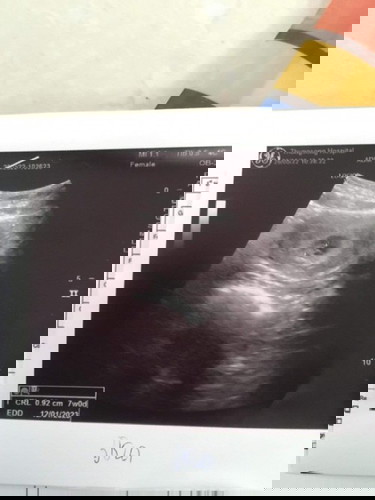

7วีคค่ะมีหัวใจแล้ว❤️ขอดูภาพอันเตอร์ซาวด์ของแม่ๆหน่อยค่ะ7วีค #ท้องแรกดีใจมากก รอมา2ปี🥰🥰🥰